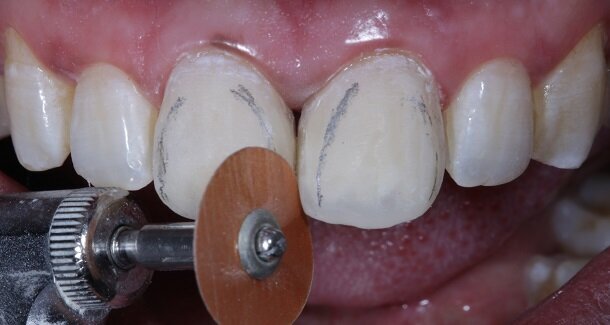

Fig 12- Gross finishing for the outline of the tooth was achieved using Red ring (composite finishing) tapered rounded bur. Almost 80% of the finishing can be done using this bur. It also helps in creating surface macro and micro anatomical variations. For better control, this bur can be used on a contra-angled hand-piece along with a convertor.

Fig 13 and 14 -Transitional Line angles were marked using a pencil and made prominent using medium grit 3M Soflex Discs proximally. The apparent faces of both the teeth were thus, created.

Fig 15 and 16 - For the surface texture; vertical surface macro-anatomy showing developmental grooves (mesial and distal) were marked using a pencil and created using the red ring finishing bur.